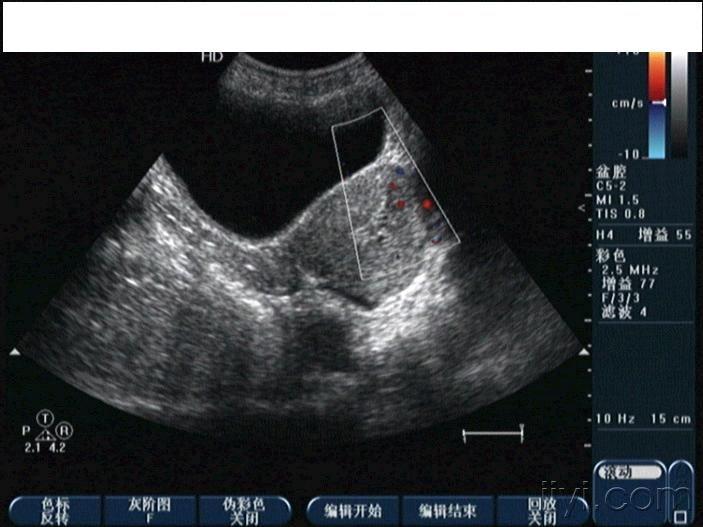

子宫穿孔超声表现图

子宫穿孔超声表现图,子宫穿孔超声图片

子宫穿孔超声图片

子宫穿孔彩超下表现

子宫穿孔彩超图

子宫穿孔b超图片